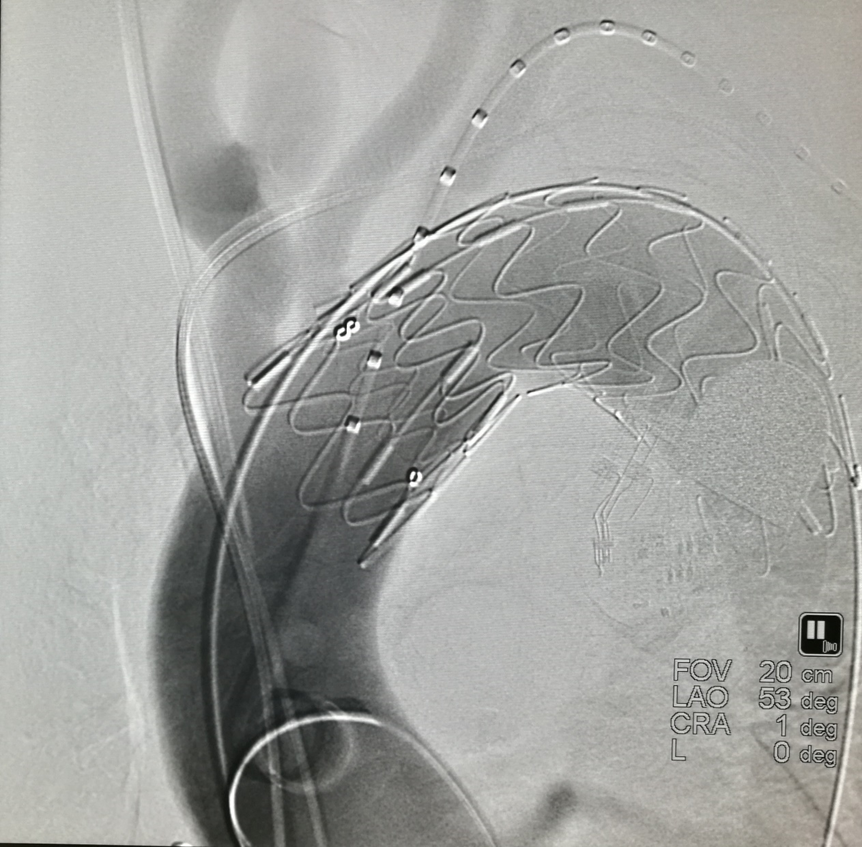

后释放支架预开窗病例

具体操作分两种模式:

预置模式:

先将器械送入主动脉,在目标分支开口处预张开前盘;

轻微回拉,使盘片卡住分支开口边缘;

再释放主体覆膜支架;

最后通过内置破膜针垂直穿透覆膜支架,完成开窗。

在主动脉内张开,轻轻牵张,使其卡在分支开口